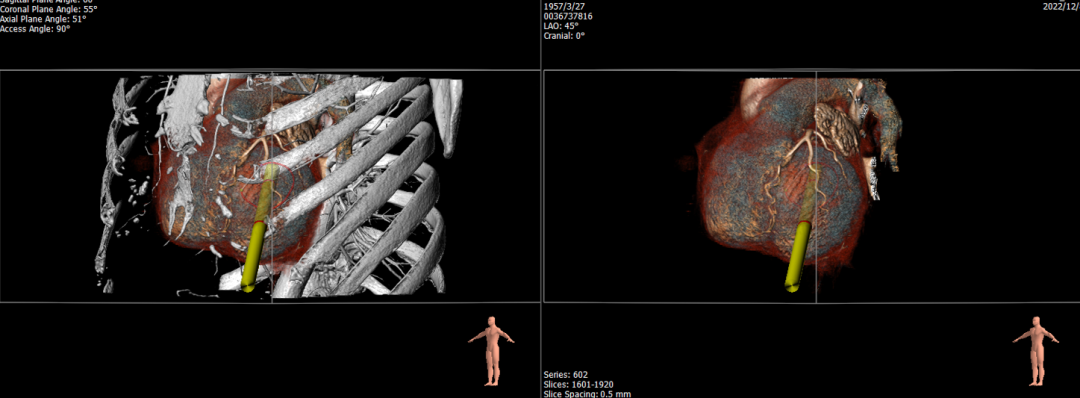

经华西医院心外科MDT团队综合评估,该患者为老年重度FMR患者,考虑外科瓣膜置换手术风险极高,决定进行MitraFix®经心尖二尖瓣植入。术前心脏CTA瓣环面积折算最大直径37 mm 模拟植入34号二尖瓣瓣膜, 收缩末心室Neo LVOT面积约230mm²。

术前心尖入路评估

手术采用左侧第六肋间微创5cm切口心尖入路,在超声引导下,清晰识别MitraFix®输送系统准确跨瓣,并将人工瓣膜准确释放于二尖瓣瓣环,瓣膜释放后支架贴合牢固,术后无反流,二尖瓣前向血流通畅、跨瓣压差3mmHg,左心室流出道通畅,流出道血流速度为1.0m/s. 后顺利撤出输送系统,关闭心尖切口,手术顺利结束。